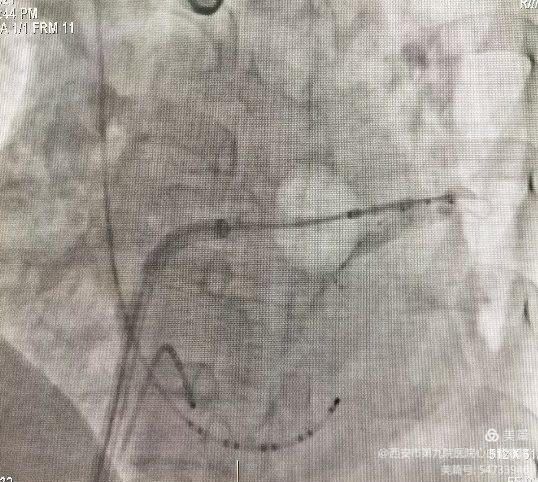

冷冻后验证肺静脉隔离完全。冷冻消融大约持续1小时顺利结束。继之进行左心耳封堵术。左心耳造影测量深度及基底部宽度:

根据造影结果,选择了匹配封堵器,并沿鞘管将封堵装置推送至左心耳内,在食道超声引导下精准定位符合”PASS”原则完成 Watchman 封堵器的释放。封堵后左心房造影显示未见明显残余漏,手术过程均非常顺利。